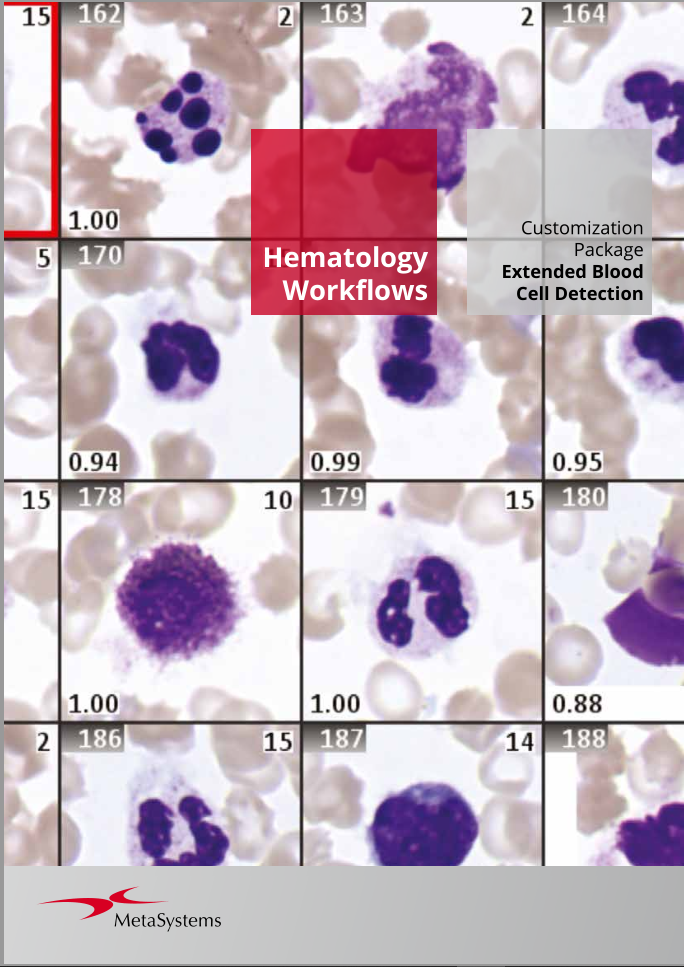

Metafer’s classifier system brings smart automation to object recognition. Combining advanced algorithms with user-defined criteria, it lets users categorize samples quickly while keeping workflows consistent and reliable. With integrated Deep Neural Networks (DNN), Metafer handles diverse sample types with precision, flexibility, and intelligence.

Customization Packages

To help you get the most out of this modular workflow approach, our Customization Packages offer more than a standard setup: they deliver a comprehensive service for configuring Metafer precisely to your task. Drawing on extensive experience from similar installations, our application specialists work closely with your team to define and refine the optimal workflow for your laboratory. This expert support accelerates the path from installation to user validation and routine operation, ensuring a faster, more confident start.

MetaSystems offers Customization Packages for application workflows that have been successfully implemented for customer labs using standard Metafer platform functionality. It is expected that they can be implemented for other customer labs using similar workflows and slide preparation procedures. If a Customization Package is purchased, MetaSystems product specialists will – based on their experience from other similar application cases - support the customer lab in adapting the Metafer software configuration to their needs. The performance of the solution will depend on the quality of the customer slides and the expertise of the users, MetaSystems cannot specify or guarantee any performance parameters. The validation of the solution for clinical use is the sole responsibility of the customer lab.